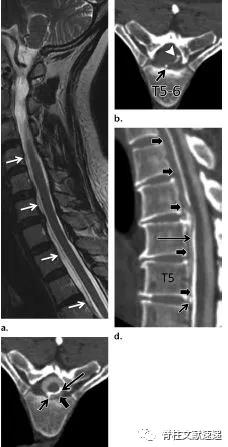

图注:背侧硬膜外椎间盘突出

图注:术前诊断倾向于硬膜外脓肿,术中见病灶呈致密纤维状,组织病理学检查显示纤维软骨盘伴反应性改变。

3.症状性胸椎间盘突出

- 在CT脊髓造影或MR成像中,当突出占椎管40%以上时,称为巨大突出。这些巨大的胸椎间盘突出症通常有密集的钙化,并有侵蚀硬脑膜的倾向。20%的人为无症状的胸椎间盘突出。有症状的胸椎间盘突出,尤其是需要手术的胸椎间盘突出少见。

- 对于有症状的胸椎间盘突出症,最常见的表现是疼痛。局限性疼痛的发生率与轴性疼痛相似,均大于根性疼痛的发生率。大约60%的患者出现脊髓病伴运动障碍,反射亢进或痉挛,感觉障碍的临床表现。膀胱功能障碍不太常见。脊髓病很少是急性的。当椎间盘巨大时,脊髓病的发生率显著增加。

图注:64岁女性,硬膜内胸椎间盘突出症,表现为进行性胸背痛和脊髓损害症状。术中见椎间盘骨赘复合体与硬脑膜紧密粘连。病理组织学检查示椎间盘组织和纤维化伴局灶性炎症改变。